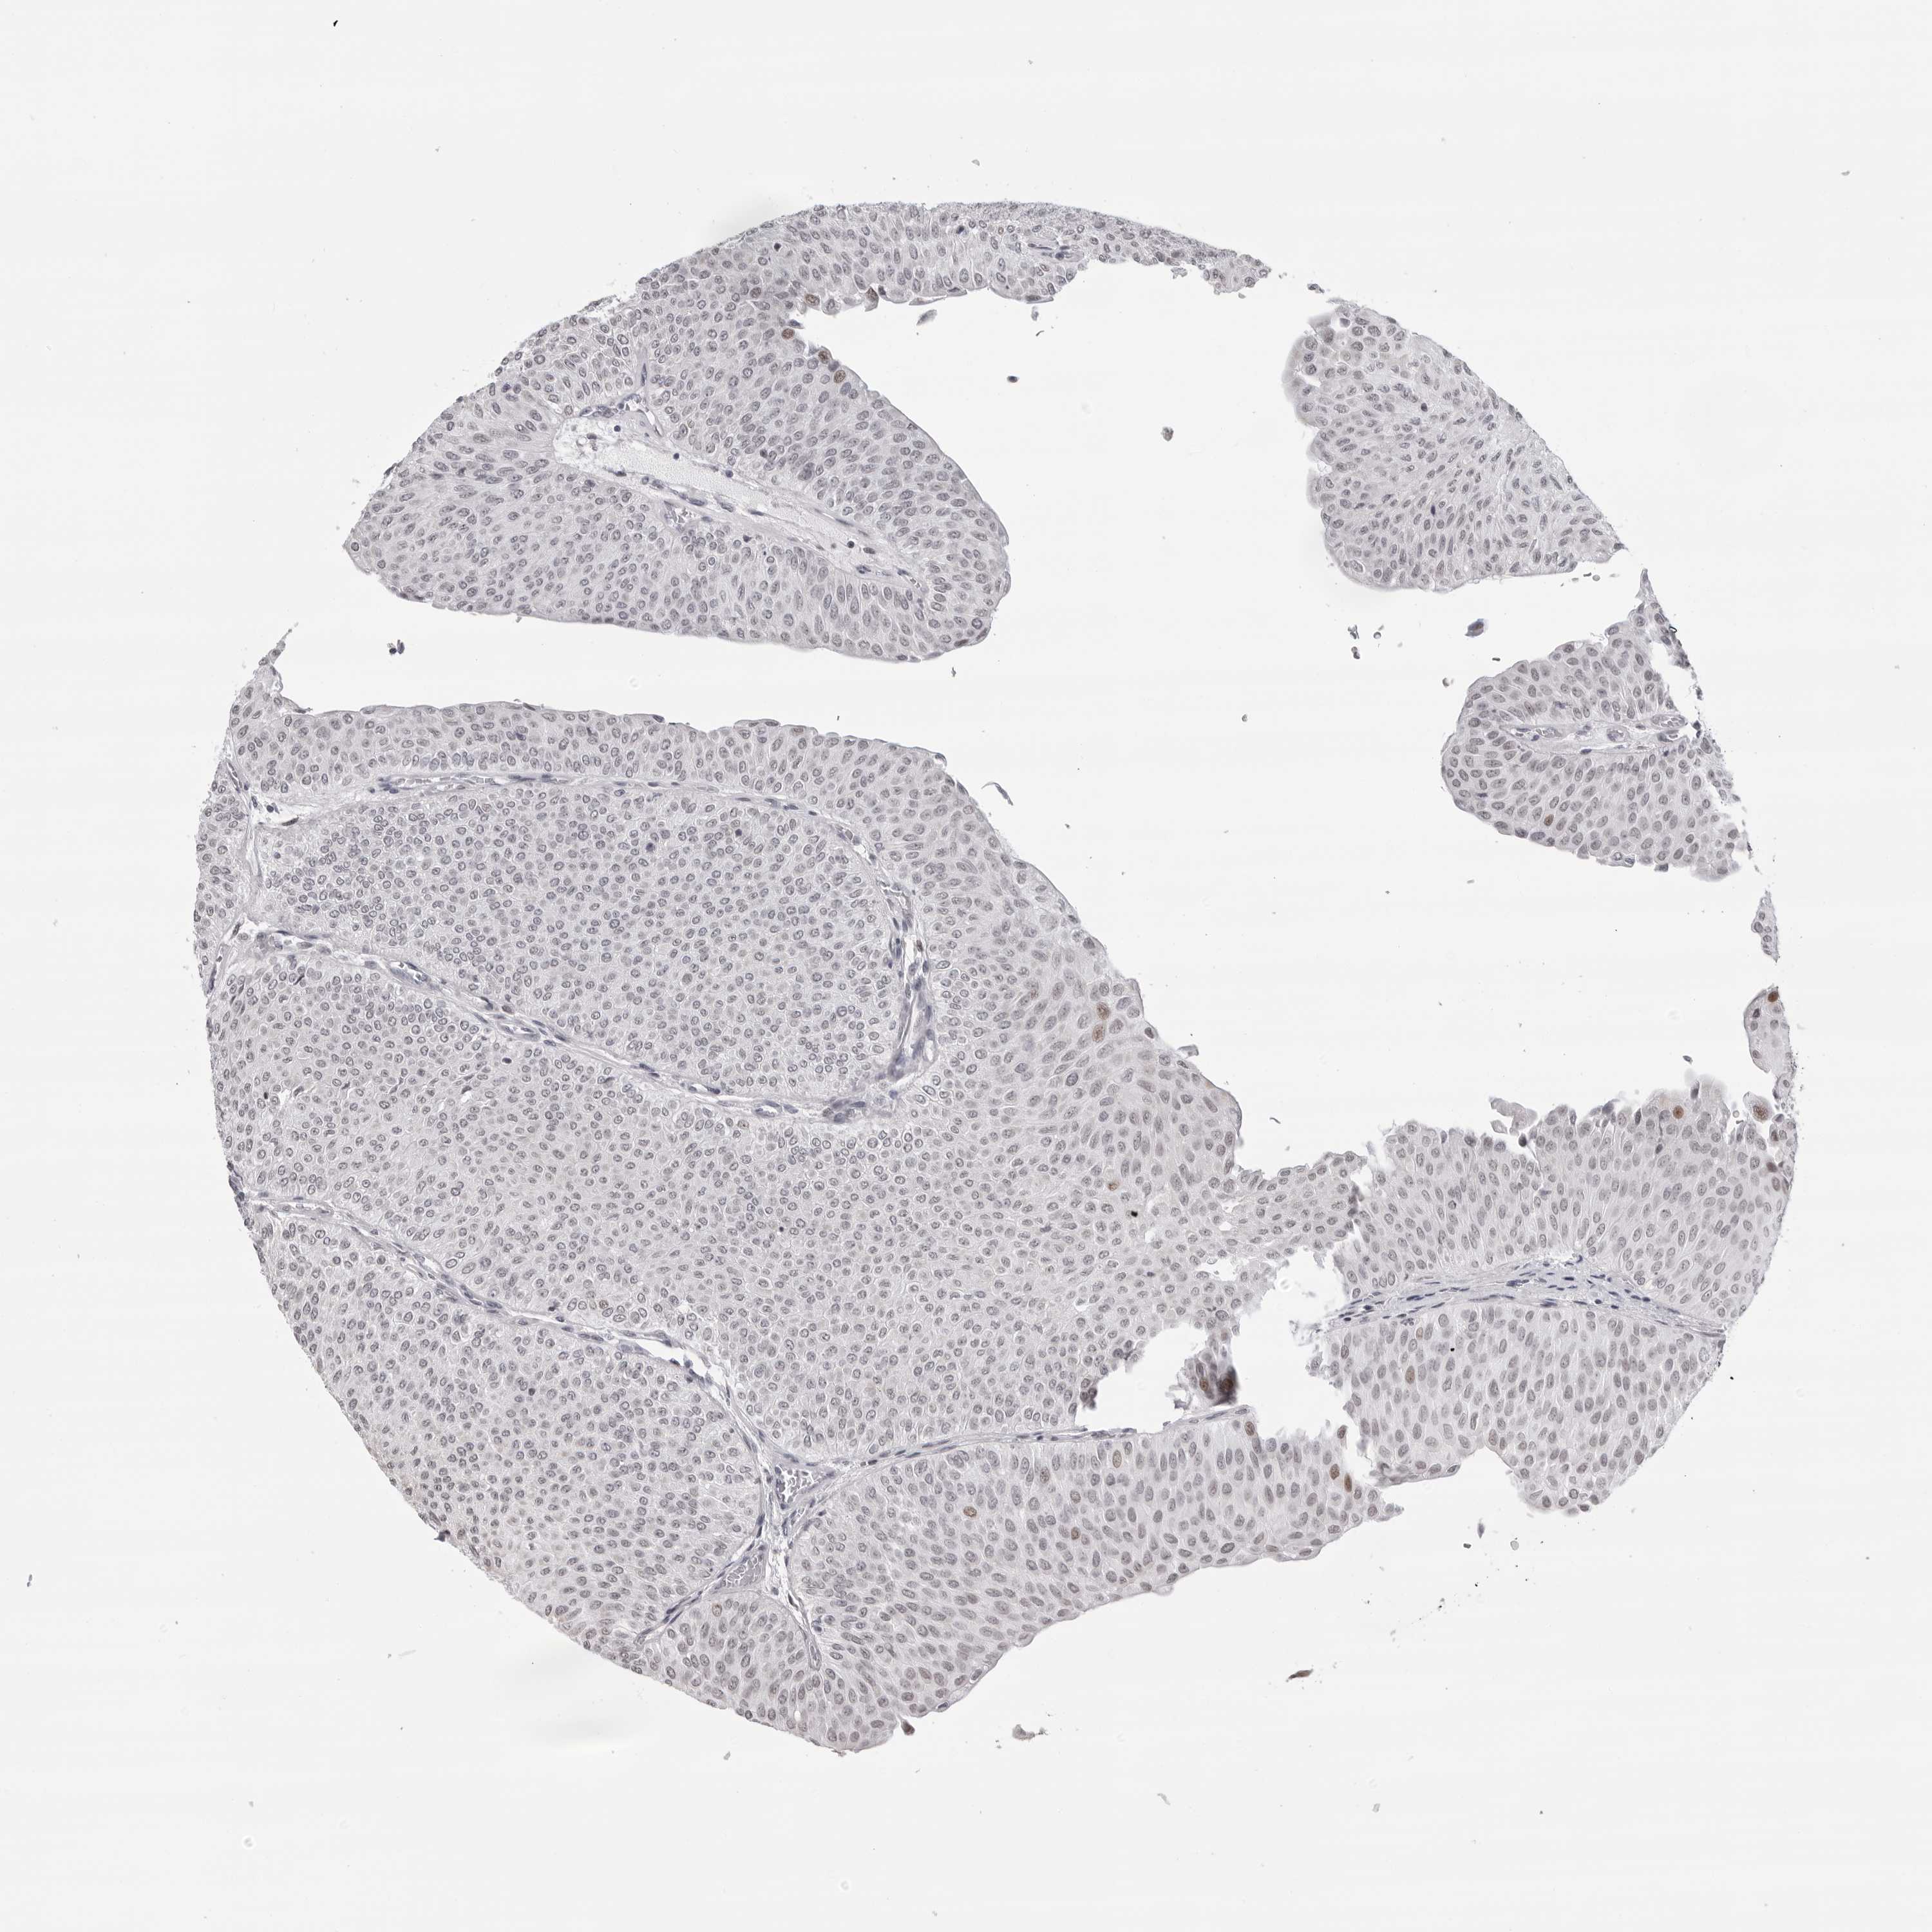

UROTHELIAL CANCER - Protein expressioni

A mouse-over function shows sample information and annotation data. Click on an image to view it in a full screen mode. Samples can be filtered based on level of antibody staining by selecting one or several of the following categories: high, medium, low and not detected. The assay and annotation is described here.

Antibody stainingi

Antibody staining in the annotated cell types in the current human tissue is reported as not detected, low, medium, or high, based on conventional immunohistochemistry profiling in selected tissues. This score is based on the combination of the staining intensity and fraction of stained cells.

Each image is clickable and will lead to virtual microscopy that enables deeper exploration of all samples and also displays staining intensity scores, fraction scores and subcellular localization as well as patient and tissue information for each sample.

Antibody HPA024676

Antibody HPA025763

Staining

High

Medium

Low

Not detected

Intensity

Strong

Moderate

Weak

Negative

Quantity

>75%

75%-25%

<25%

None

Location

Nuclear

Cytoplasmic/membranous

Cytoplasmic/membranous,nuclear

Urothelial carcinoma, High grade